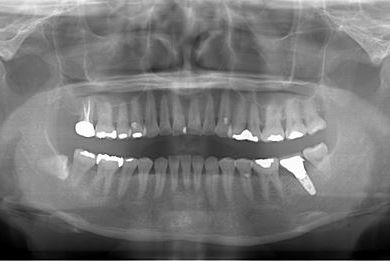

性別/年齢 女性 / 54歳

主訴 抜歯したところのインプラント治療を希望。

治療内容 インプラント1本、メタルボンドセラミック1本

総治療費 252,000円

治療期間 4ヶ月

治療前

• 治療前